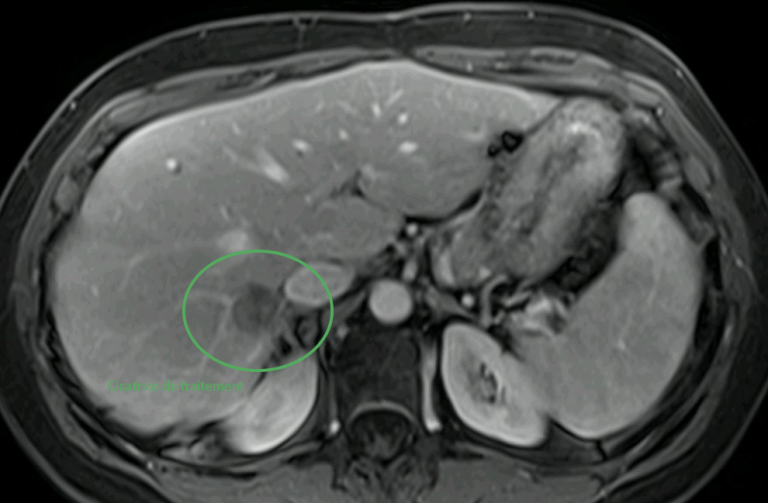

Cas clinique : une prise en charge personnalisée et combinée

L’exemple de Mme F., 50 ans, illustre parfaitement l’intérêt de ces techniques.

Suivie pour un cancer colorectal métastatique, elle présente une nouvelle récidive avec :

• une métastase pulmonaire de 2,5 cm, située près de structures centrales,

• une métastase hépatique de 1 cm, profonde et difficilement accessible chirurgicalement.

Traitement hépatique par micro-ondes

Dans un second temps, la métastase hépatique est traitée par thermoablation micro-ondes, avec protection des organes voisins grâce à une technique d’hydrodissection.

En images

Images du traitement des organes (poumon et foie) avant, pendant et après le traitement.